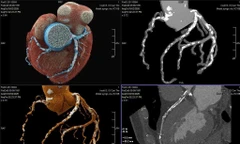

TPO - Một cơn đau ngực dữ dội do nhồi máu cơ tim cấp dẫn tới biến chứng rối loạn nhịp ác tính khiến người đàn ông rơi vào nguy kịch. Tại Bệnh viện Quân y 175, bệnh nhân liên tiếp ngừng tim trên bàn cấp cứu khiến các bác sĩ phải chạy đua từng phút để giành lại sự sống.